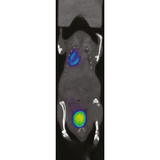

The β-CUBE is our high-performance preclinical PET imager.

Sub-millimeter image resolution is achieved through the combination of monolithic scintillators, the latest photon counting technology and GPU-based event positioning and iterative image reconstruction. The 5-ring configuration ensures best-in-class sensitivity over a field-of-view adequate for whole-body mouse and rat imaging at high count rate. In-house hardware allows for dynamic and gated studies. Intuitive and wireless acquisition software combined with our multimodal small animal bed allow for easy and modular multimodal imaging along with the γ-CUBE (SPECT) and X-CUBE (CT).